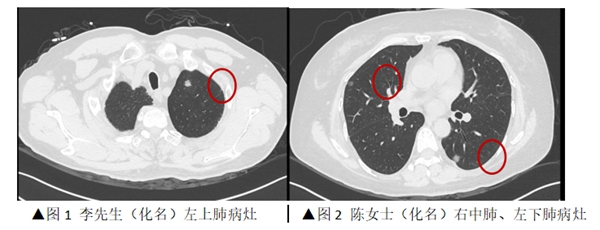

近日,老虎机app (简称老虎机app )心胸外科为一对“夫妻肺癌”患者,在同一天内实施了胸腔镜下微创肺癌切除手术。妻子顺利完成了双侧肺结节切除,丈夫则接受了单侧肺结节切除,术后两人均恢复良好,并在同一天康复出院。半月前,家住海南省的李先生(化名)和陈女士(化名)通过线上问诊的形式,联系到了我院心胸外科主任刘振国教授,并在刘振国教授的建议下进行了胸部CT检查,结...